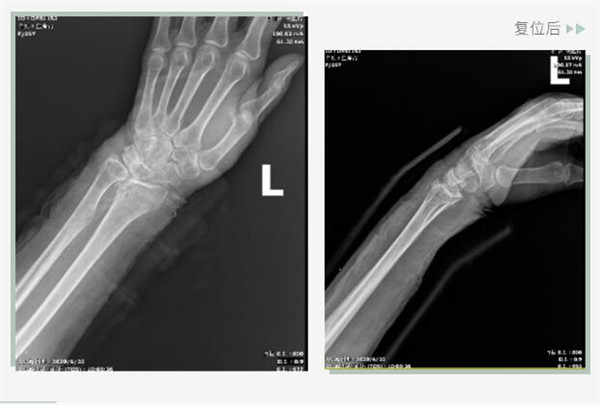

25日當(dāng)天,莊阿婆來(lái)到危立軍副院長(zhǎng)門診,經(jīng)拍片顯示,莊阿婆左橈骨遠(yuǎn)端粉碎性骨折,左髂骨至髖臼后緣及恥骨下支骨折??紤]到莊阿婆年紀(jì)較大,基礎(chǔ)病較多,難以經(jīng)受手術(shù)創(chuàng)傷,傳統(tǒng)手法復(fù)位更為合適。推、拽、按、捺……經(jīng)過(guò)危立軍副院長(zhǎng)一番手法復(fù)位后,再次拍片顯示莊阿婆橈骨遠(yuǎn)端骨折端復(fù)位位置良好,莊阿婆及其家人感到非常滿意。

復(fù)位后